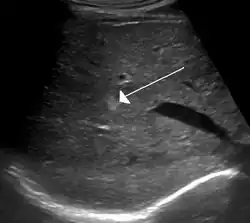

Gradient-echo T2WI magnetic resonance imaging (MRI) is the most sensitive method for diagnosing cavernous hemangiomas.[21] MRI is such a powerful tool for diagnosis that it has led to an increase in diagnosis of cavernous hemangiomas since the technology's advent in the 1980s.[16] The radiographic appearance is most commonly described as "popcorn" or "mulberry"-shaped.[22] Computed tomography (CT) scanning is not a sensitive or specific method for diagnosing cavernous hemangiomas.[23] Angiography is typically not necessary, unless it is required to rule out other diagnoses. Additionally, biopsies can be obtained from tumor tissue for examination under a microscope. It is essential to differentially diagnose cavernous hemangioma because treatments for these lesions are less aggressive than that of cancerous tumors, such as angiosarcoma. However, since MRI appearance is practically pathognomonic, biopsy is rarely needed for verification.[23]

On ultrasound, cavernous haemangiomas in liver appear as homogenous, hyperechoic lesions with posterior acoustic enhancement. On CT or MRI scans, it shows peripheral globular/nodular enhancement in the arterial phase, with portions of attenuation of enhancing areas. In the portal venous phase, it shows progressive centripetal enhancement. In delayed phase, it shows retention of contrast. It shows a high signal on T2 weighted images.[24]